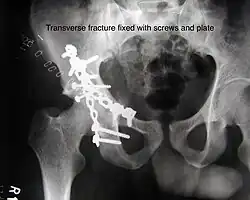

Transverse fracture fixed with screws and plate

| Transverse | In this variety of fracture, the innominate bone is broken such that the upper part consists of ilium with weight bearing dome and the lower part consists of ischium and pubic bones. It typically occurs when the injuring force is applied from the side, against the greater trochanter of the femur bone, as in a fall on the side or being hit on the side. This is a two part fracture, but though both columns are broken, it is not a true both-column fracture, as the weight bearing dome is still attached to main ilium.

In this variety of fracture, the innominate bone is broken such that the upper part consists of ilium with weight bearing dome and the lower part consists of ischium and pubic bones. It typically occurs when the injuring force is applied from the side, against the greater trochanter of the femur bone, as in a fall on the side or being hit on the side. This is a two part fracture, but though both columns are broken, it is not a true both-column fracture, as the weight bearing dome is still attached to main ilium. Depending on the level at which the fracture line passes in relation to weight bearing area, the transverse fracture is further subdivided into types:

X-ray visualization is best done in Antero posterior view and Iliac and obturator oblique views. In CT scan the characteristic feature is that the fracture line runs from front to back. CT scan also helps in identifying impaction of bone pieces and if there are pieces in the joint |